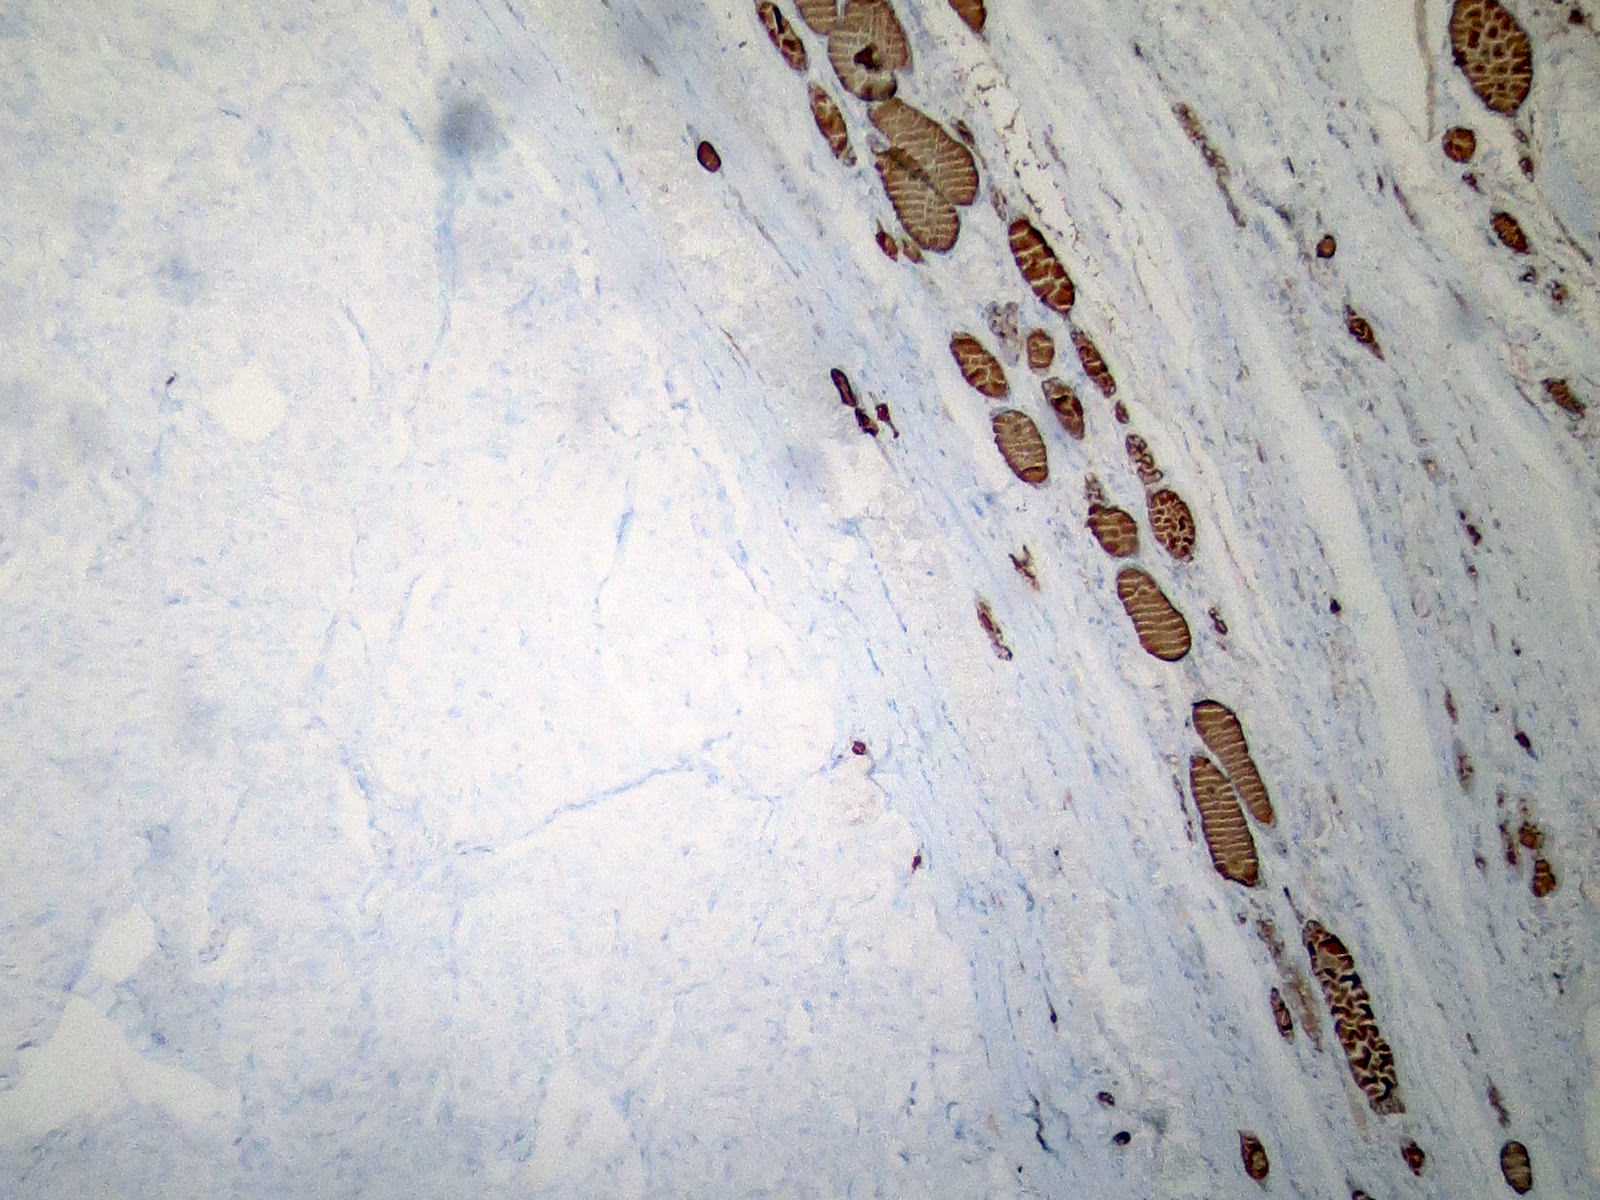

Microscopic (histologic) images

Contributed by Shuanzeng Wei, M.D., Ph.D., Joseph Christopher Castillo, M.D. and Mark R. Wick, M.D.

AFIP images

Images hosted on other servers:

Positive stains

- Calcitonin, CEA, TTF1 (weak to moderate), PAX8 (variable and weak) (Mod Pathol 2008;21:192), Congo red for amyloid